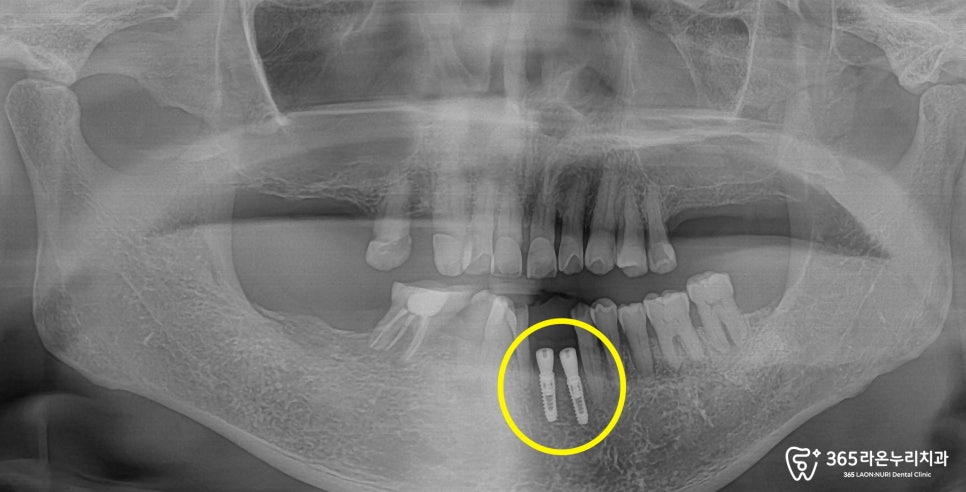

그리고 나서, 실제 구강과

엑스레이 촬영을 통해

치아의 건강 상태를

확인하게 됩니다.

왼쪽 아래 앞니가 하나 결손되어 있는 것이

먼저 관찰되며, 다른 치아들도

흔들리고 상태가 좋지 않았습니다.

특히, 결손된 앞니 부위의

골도 심하게 내려가 있었습니다.

위턱 양쪽의 어금니가 모두 사라졌고,

오른쪽의 경우 작은 어금니 하나가

없는 모습입니다.

반대편에 있는 작은 어금니 하나도 심하게

아래턱 역시도, 치조골이 많이

내려가게 되면서 치아 뿌리쪽이

많이 드러나고 있었습니다.

엑스레이를 보시면 전체적으로

치아 뿌리가 드러날 정도의

골소실이 일어나 있는 것을

더욱 명확하게 확인할 수 있었는데요.